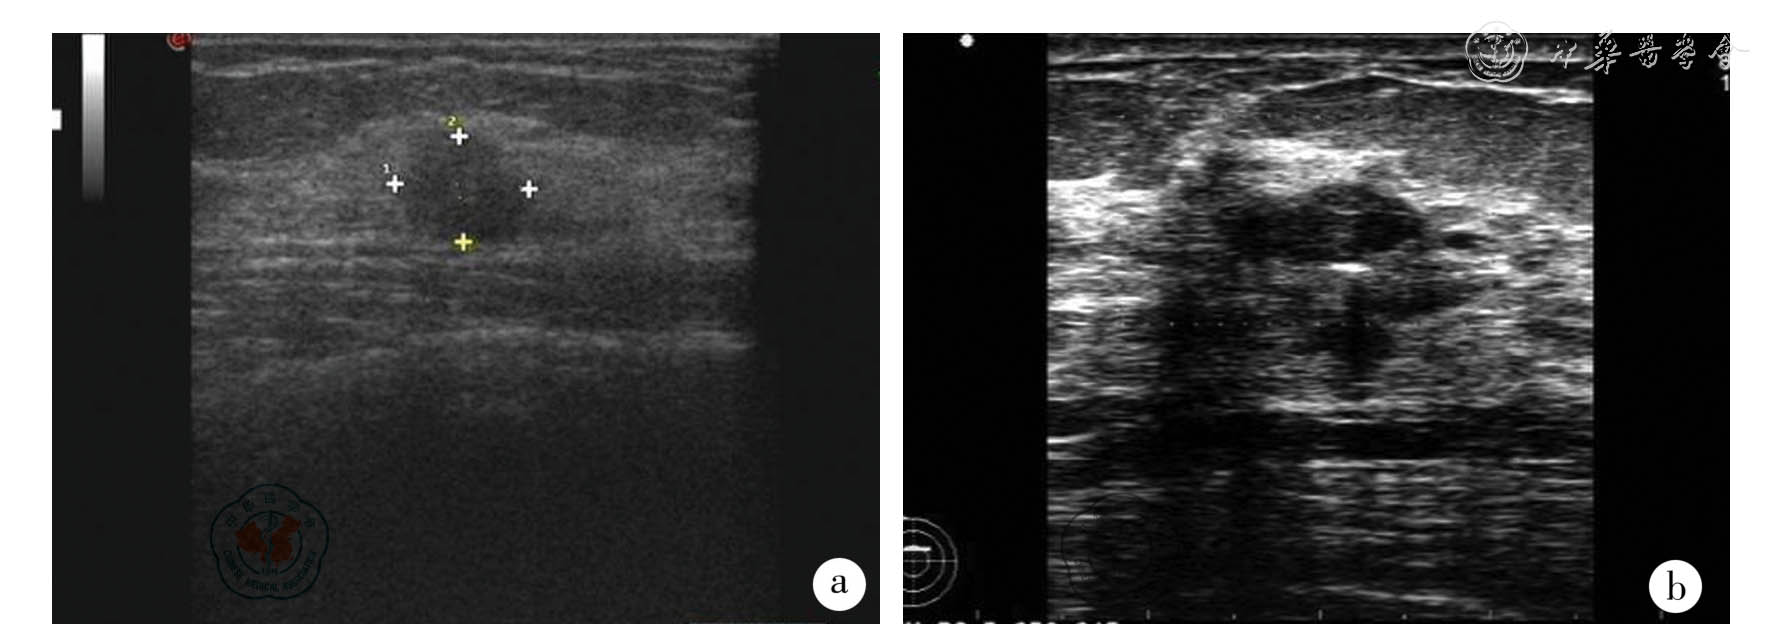

图1 2 例恶性病例术前超声图

a:50 岁患者,超声示10.6 mm (横径)×8.5 mm (纵径)低回声占位,BI-RADS 3 级,病理检查示浸润性导管癌;b:55 岁患者,超声示10.87 mm(横径)×4.82 mm(纵径)低回声占位,BI-RADS 3 级,病理结果示浸润性导管癌。